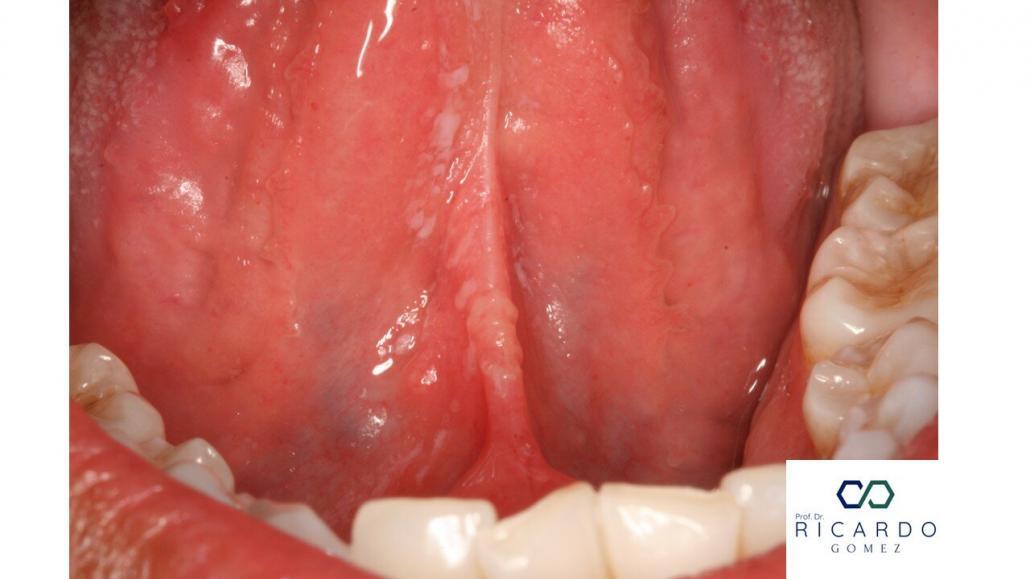

Figura 1 – Múltiplas pseudomembranas localizadas no ventre lingual de uma paciente grávida.

Caracteriza-se pela presença de pseudomembranas esbranquiçadas, removíveis à raspagem (Figura 1). As pseudomembranas são formadas por emaranhado de hifas, restos celulares e células epiteliais descamadas (Figura 2). A mucosa subjacente apresenta coloração eritematosa.

Essa forma pode ocorrer como efeito colateral ao uso de imunossupressores (corticosteroides sistêmicos ou inalados), antibióticos de amplo espectro, em pacientes com diabetes, xerostomia, ou após radioterapia/quimioterapia. Também é frequente em indivíduos imunossuprimidos (HIV e transplantados de órgãos). Casos em gestantes e recém-nascidos (pela imaturidade imunológica e microbiota oral em formação) também são descritos. Os sintomas incluem sensação de ardência na mucosa.